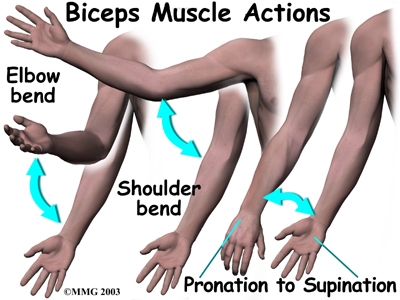

can bend the elbow upward. The biceps can also help flex the shoulder, raising the arm up. And the biceps can rotate, or twist, the forearm in a way that points the palm of the hand up. This movement is called . Supination positions the hand as if you were carrying a tray.